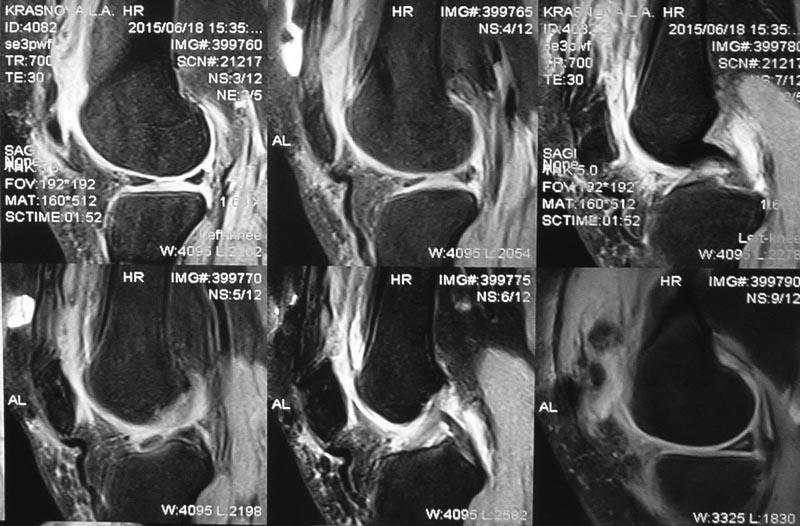

Пациентка 35лет. 3 месяца назад в одном из районов операция: артротомия левого коленного сустава, резекция внутреннего мениска.

В послеоперационном периоде, со слов пациентки, было нагноение в области послеоперационного шва, которое было быстро купировано. Прошла курс реабилитационного лечения без эффекта. В настоящее время жалобы на отсутствие активного разгибания в коленном суставе. Пассивное разгибание не ограничено. В медиальном отделе послеоперационный рубец, умеренно болезненный. На МРТ: низкое стояние надколенника.

Patient K., 35y.o. 3 months ago had arthrotomy of left knee joint, resection of the medial meniscus. In the postoperative period, according to the patient, were inflammation in the postoperative seam, which was quickly docked. He underwent a course of rehabilitation treatment without effect. Currently complaints about the lack of active extension of the knee. Passive extension is not limited. The medial postoperative scar, moderately painful.

MRI: patella baja.

Может он и раньше был низко. А вот связка надколенника скорее всего порвана. Она "извита" и имеется дефект в месте прикрепления. Отсюда и нет активного разгибания.

При действительно низком положении надколенника слева, убедиться в сохранности сухожилия квадрицепса. По МРТ его целостность сомнительна.

По моему мнению, собственная связка надколенника цела, т.к. прослеживается на всем протяжении, да и надколенник ушел бы вверх.

Сделали контрольные рентгенограммы, там с противоположной стороны вес нормально, с больной стояние надколенника низкое.

Учитывая, что разрез сделан поперек сустава, то мне представляется, что просто была очень грубо сшита капсула. Отсюда и сморщенная собственная связка надколенника. Разгибание вы описали, а что со сгибанием? Какова подвижность надколенника?